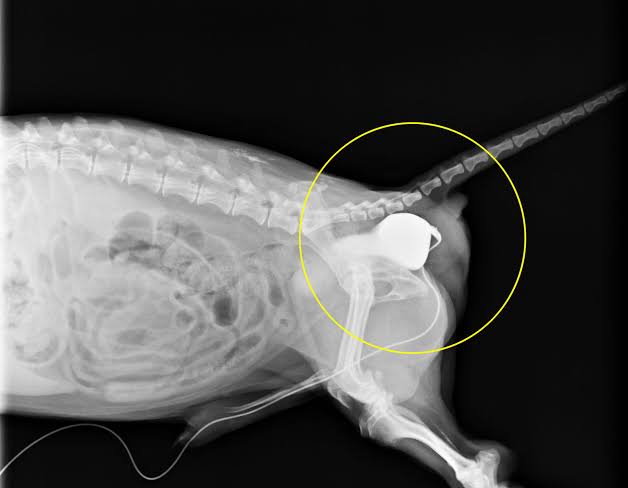

症状として、各種臓器や脂肪が飛び出ることで排便や排尿に支障をきたしますが、膀胱が飛び出て反転している場合などは排尿が困難になり一刻を争う事態になります。

まず、排尿困難な場合、カテーテル挿入を試みて排尿ルートを確保します。

しかし、膀胱が反転していたらする場合 挿入が困難であり無理やりやると膀胱破裂や尿道損傷を伴う場合があるため難しい場合には外科的処置を行うべきでしょう。